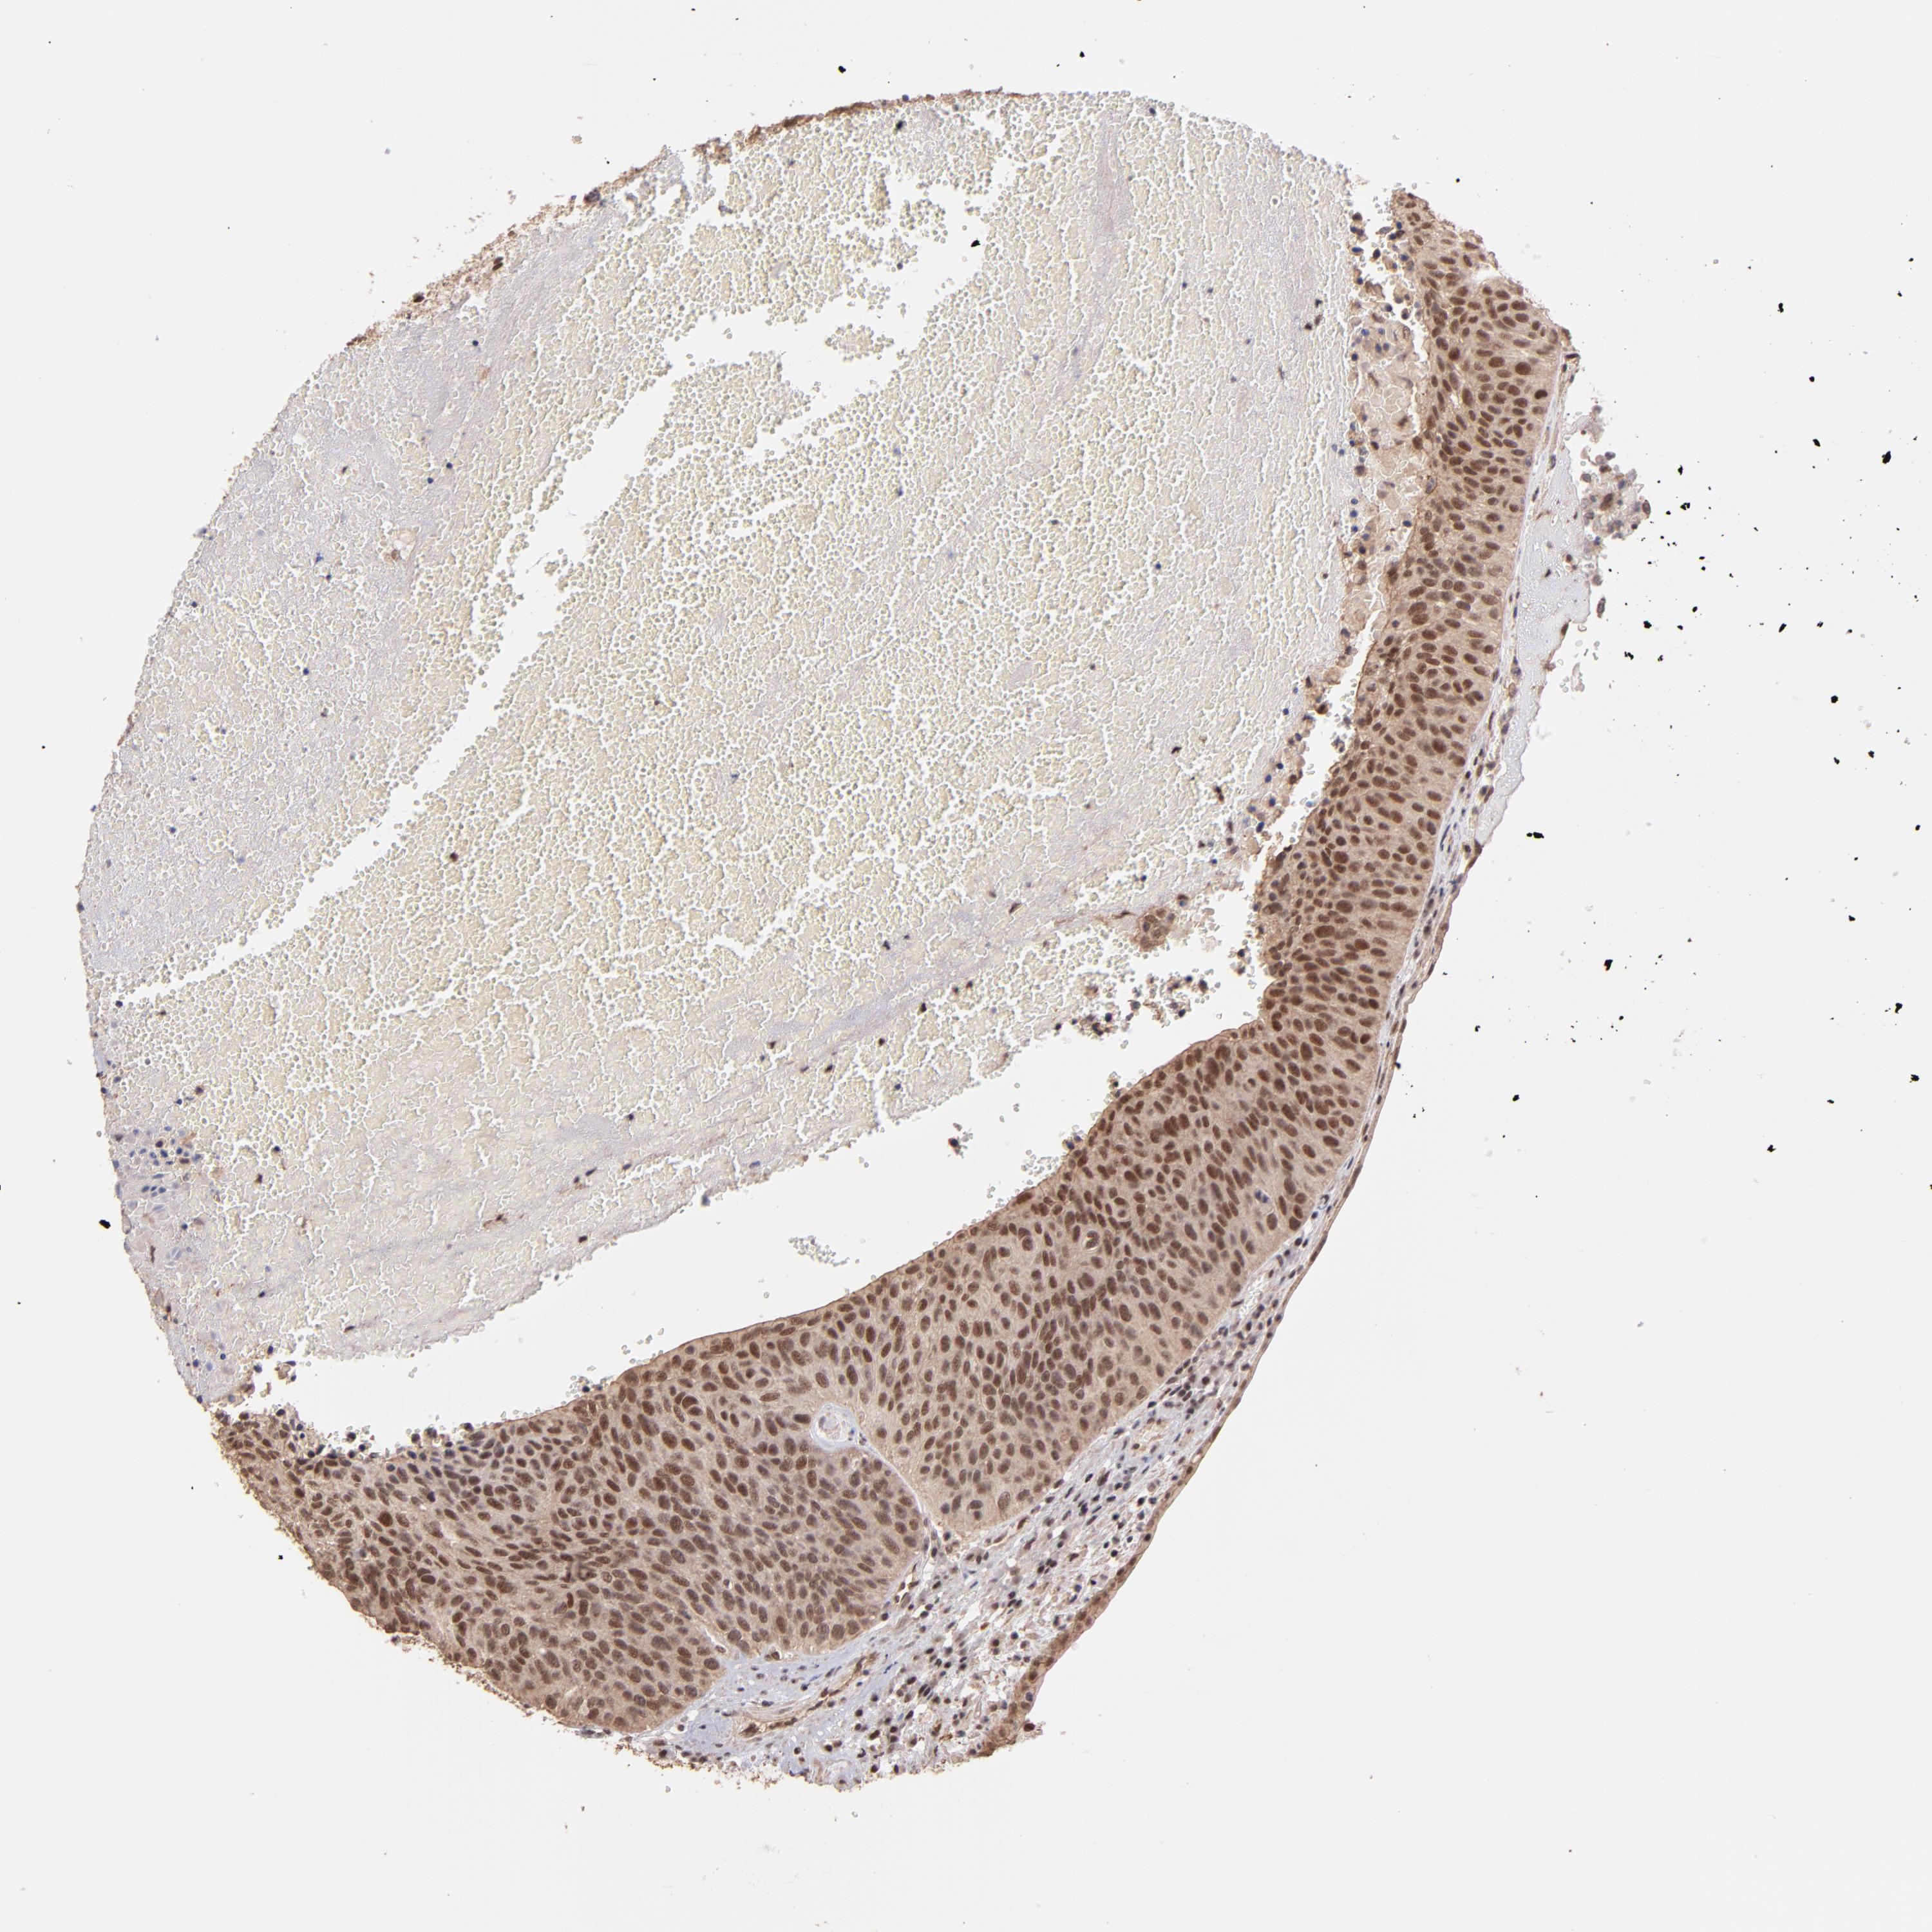

UROTHELIAL CANCER - Protein expressioni

A mouse-over function shows sample information and annotation data. Click on an image to view it in a full screen mode. Samples can be filtered based on level of antibody staining by selecting one or several of the following categories: high, medium, low and not detected. The assay and annotation is described here.

Note that samples used for immunohistochemistry by the Human Protein Atlas do not correspond to samples in the TCGA dataset.

Antibody stainingi

Antibody staining in the annotated cell types in the current human tissue is reported as not detected, low, medium, or high, based on conventional immunohistochemistry profiling in selected tissues. This score is based on the combination of the staining intensity and fraction of stained cells.

Each image is clickable and will lead to virtual microscopy that enables deeper exploration of all samples and also displays staining intensity scores, fraction scores and subcellular localization as well as patient and tissue information for each sample.

Antibody HPA001907

Antibody HPA002735

Antibody CAB010451

Antibody CAB080271

Staining

High

Medium

Low

Not detected

Intensity

Strong

Moderate

Weak

Negative

Quantity

>75%

75%-25%

<25%

None

Location

Nuclear

Cytoplasmic/membranous

Cytoplasmic/membranous,nuclear

Urothelial carcinoma, High grade

Urothelial carcinoma, Low grade

Adenocarcinoma, NOS